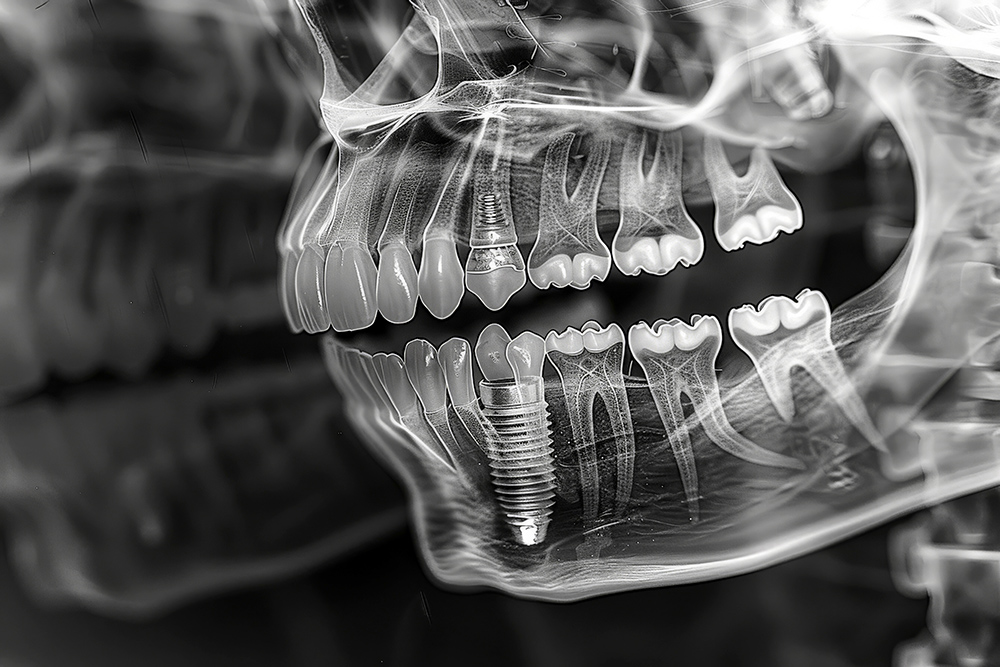

임플란트 시술 전, 의사는 환자와 초기 상담을 진행하며 환자의 요구사항과 건강 상태를 확인합니다. 이때 X-ray 촬영, 3D CT 스캔 등을 통해 환자의 구강 구조를 면밀히 분석합니다. 이 과정을 통해 시술 계획이 구체적으로 잡히며, 필요시 추가적인 치료(예: 뼈이식)가 논의될 수 있습니다.

2. 치조골 준비 과정

만약 치조골이 부족한 경우, 뼈이식 수술이 필요할 수 있습니다. 이 과정은 임플란트를 안전하게 고정할 수 있도록 하기 위함이며, 뼈이식 후 회복 기간은 최소 3개월에서 6개월 정도 소요됩니다. 이 시기를 통해 이식된 뼈가 단단히 자리 잡게 됩니다.